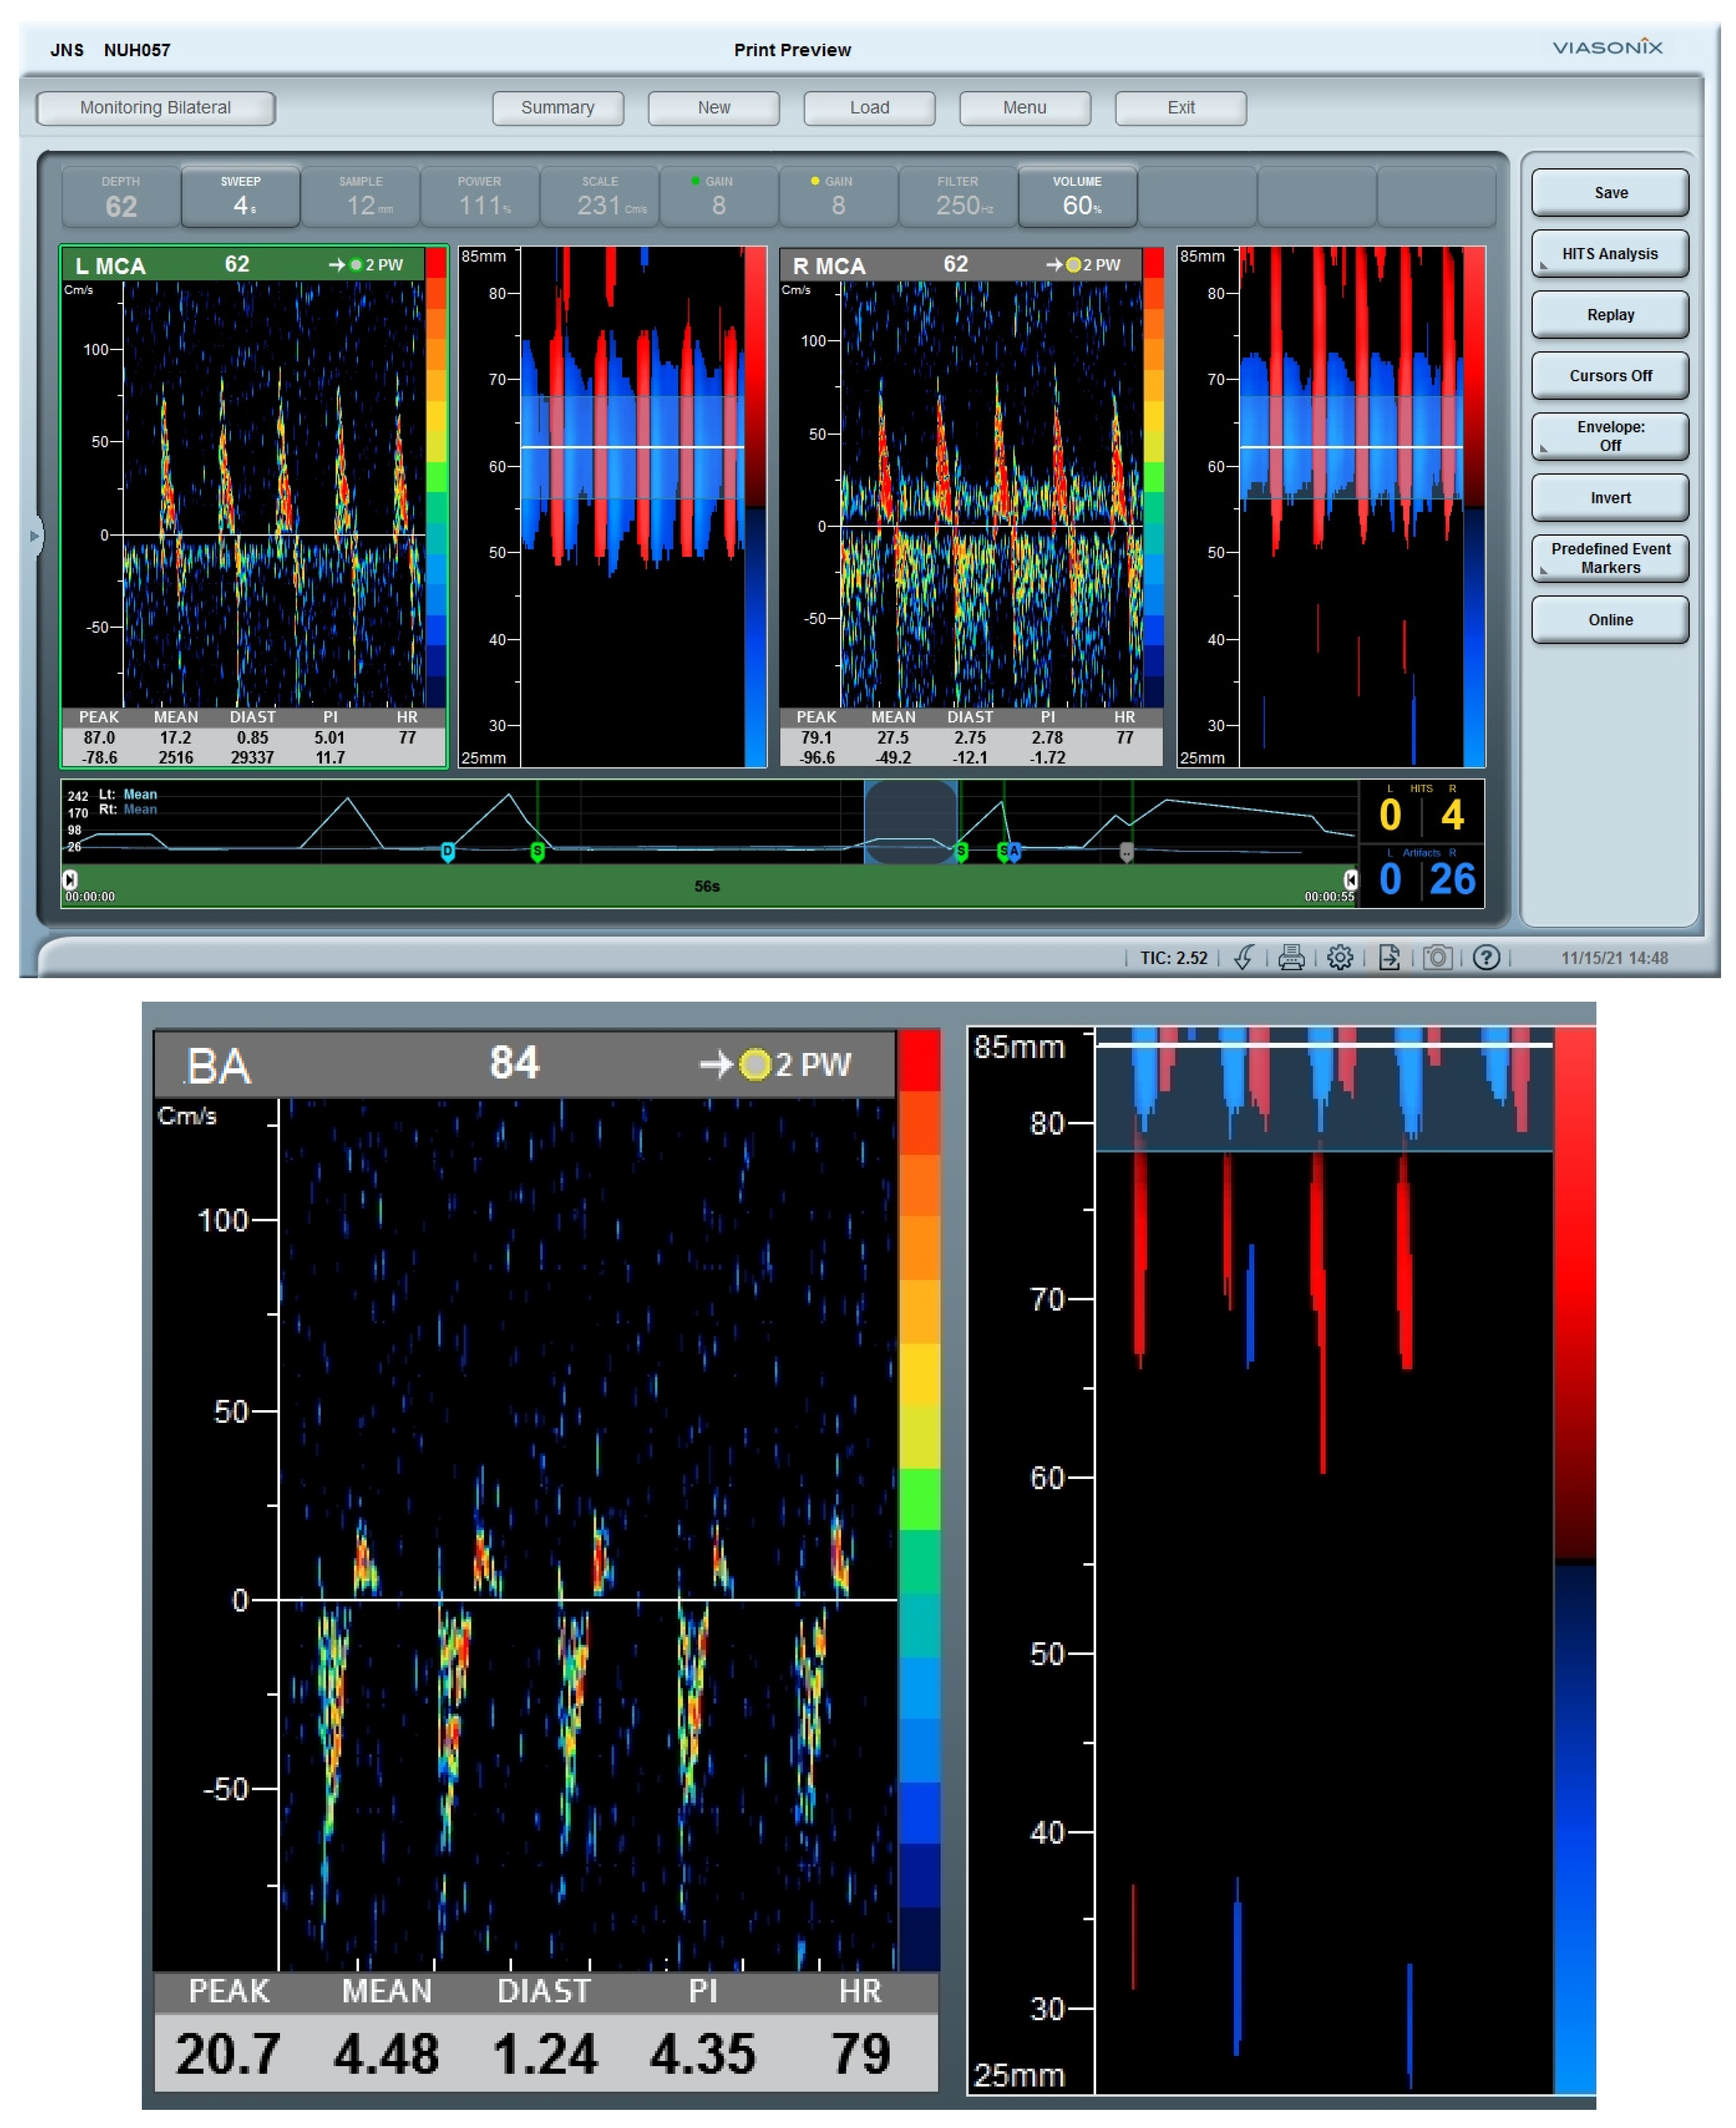

3.2. Patient B